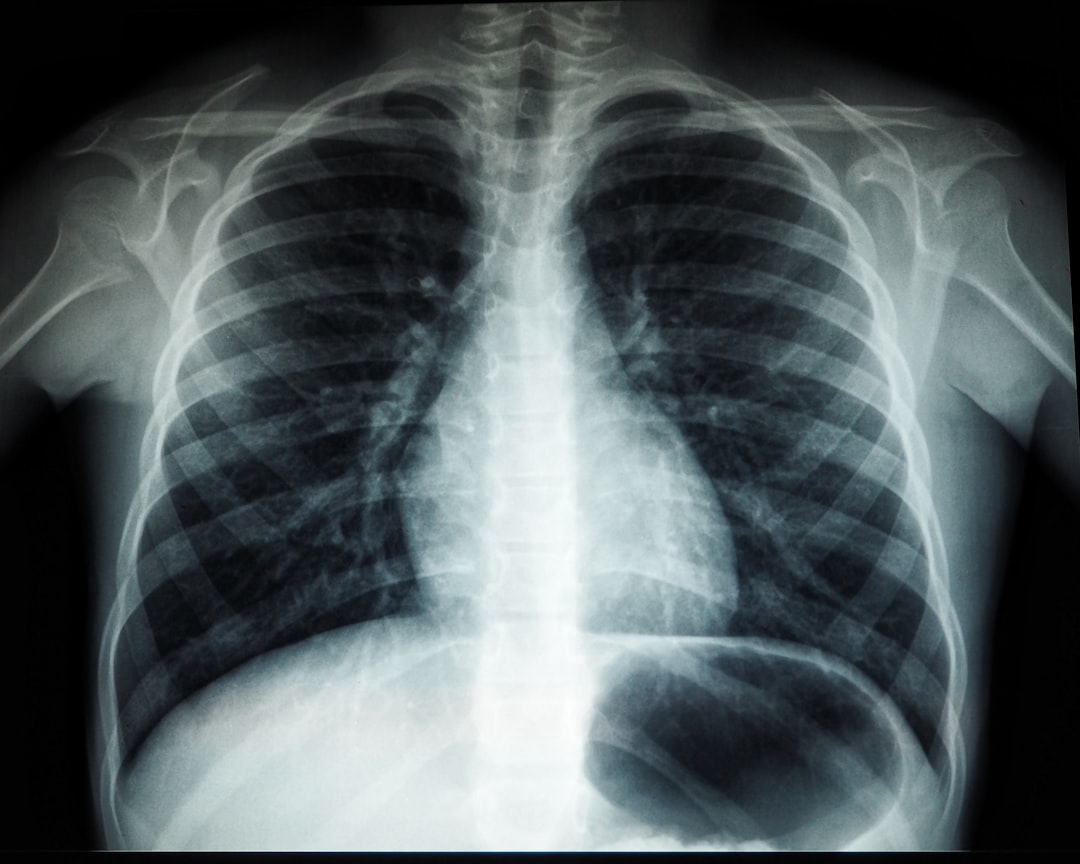

Photo health lungs